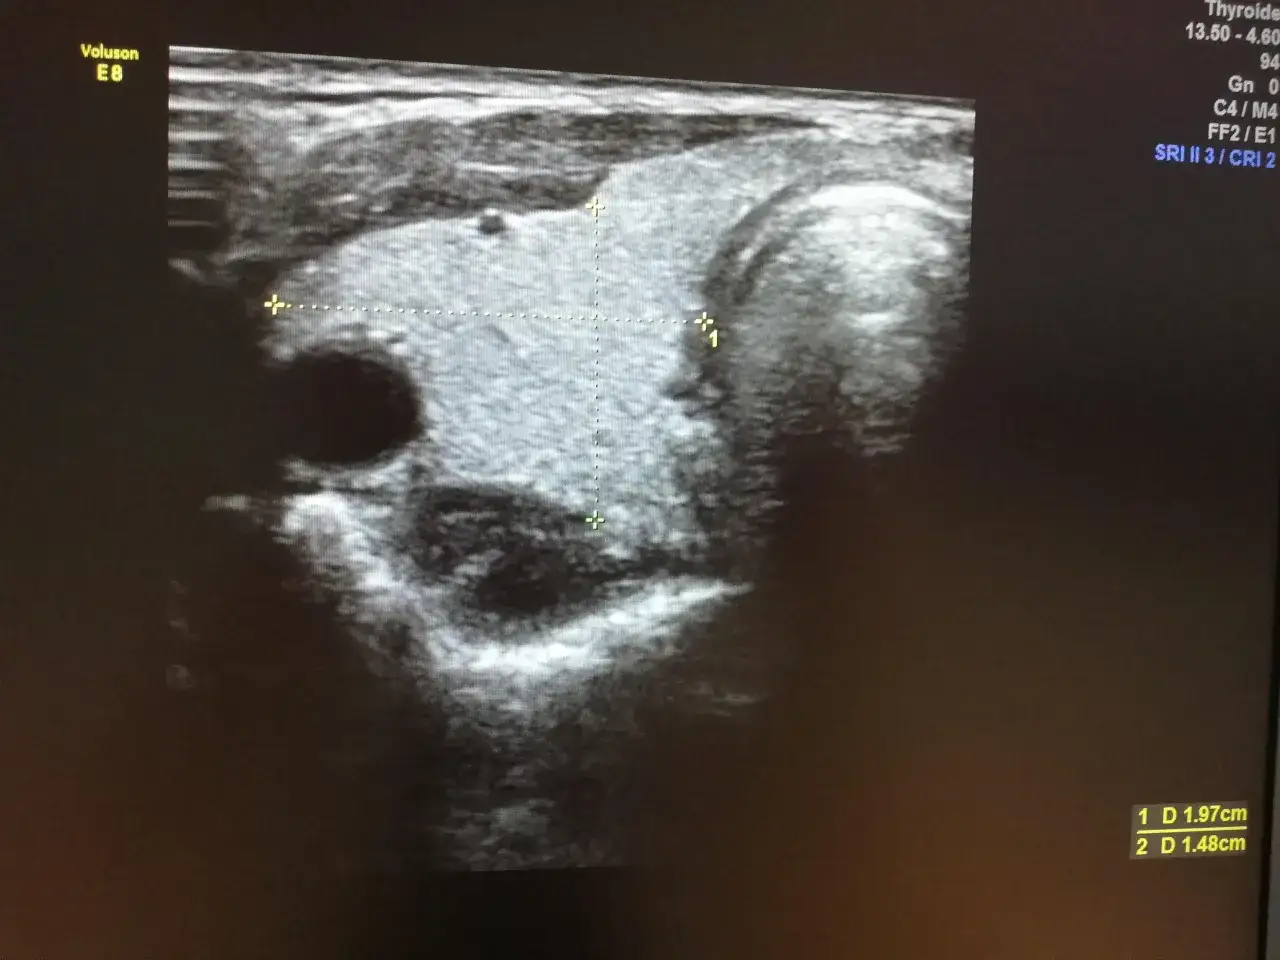

Badania laboratoryjne, takie jak oznaczenie poziomu TSH (hormonu tyreotropowego), są niezwykle ważne w diagnostyce chorób tarczycy, jednak często nie dostarczają pełnego obrazu stanu gruczołu. Ultrasonografia (USG) stanowi cenne uzupełnienie, pozwalając na ocenę morfologiczną tarczycy jej wielkości, kształtu, jednorodności miąższu oraz obecności ewentualnych zmian ogniskowych, takich jak guzki czy torbiele. Jest to badanie nieinwazyjne i bezbolesne. Aby uzyskać jak najbardziej wiarygodny wynik, nie jest wymagane specjalne przygotowanie. Warto jednak ubrać się w luźne ubranie, które nie uciska szyi, a także poinformować lekarza o wszystkich przyjmowanych lekach, zwłaszcza tych wpływających na pracę tarczycy.

W opisie USG mogą pojawić się również informacje o mikrozwapnieniach lub zmianach ogniskowych, takich jak guzki czy torbiele. Mikrozwapnienia, czyli bardzo drobne złogi wapnia, mogą być niekiedy markerem zwiększonego ryzyka złośliwości zmiany i wymagają szczególnej uwagi. Podobnie, obecność guzków czy torbieli, zwłaszcza jeśli są duże, szybko rosnące lub mają niepokojące cechy w obrazie USG, może wymagać dalszej diagnostyki, takiej jak biopsja cienkoigłowa (BAC) lub regularna obserwacja.